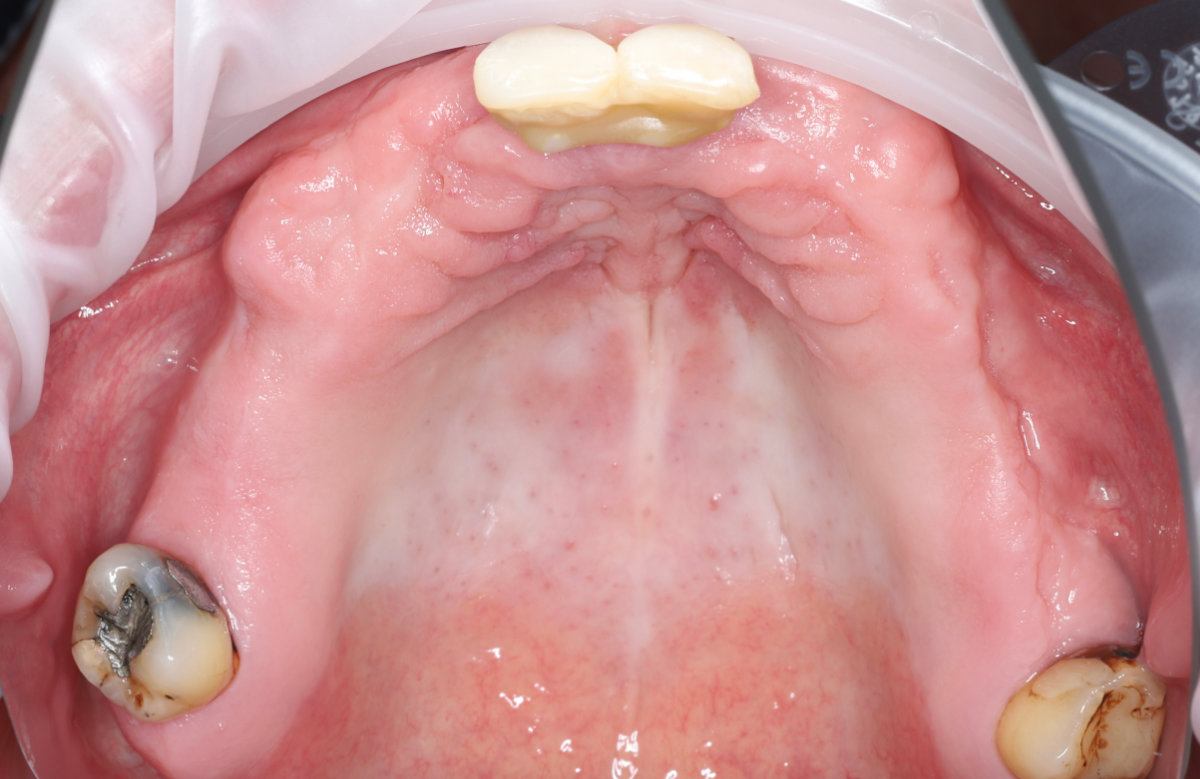

Navigovaná chirurgia, 5 implantátov

Autor práce Dr. Michal Repaši

Zubný technik Vasil Csopej